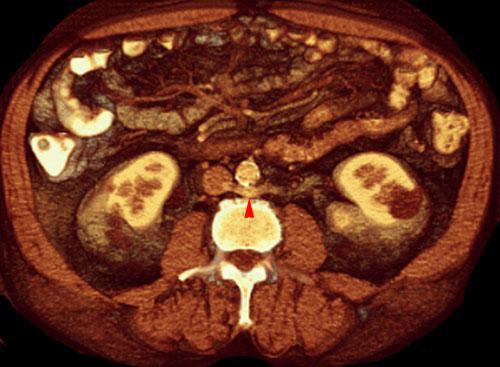

Vena renal izquierda circumaórtica

VR seccional. Visión axial caudal. TC contrastado en fase venosa. Una sección mas caudal muestra la rama inferior de la vena circumaórtica (punta de flecha) en su paso retroaórtico hacia la vena cava inferior